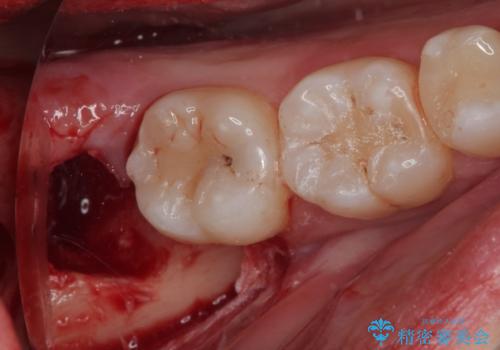

- 親知らずを抜きたいとのことで来院された患者様です。

CTで神経の位置などを確認し、抜歯術を行いました。

しっかり麻酔が効いたことを確認してから安全に抜歯を行いました。